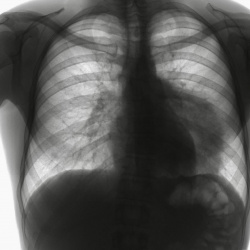

Пациентка 70 лет. Переболела КОВИДом. Жалобы на кровохарканье.